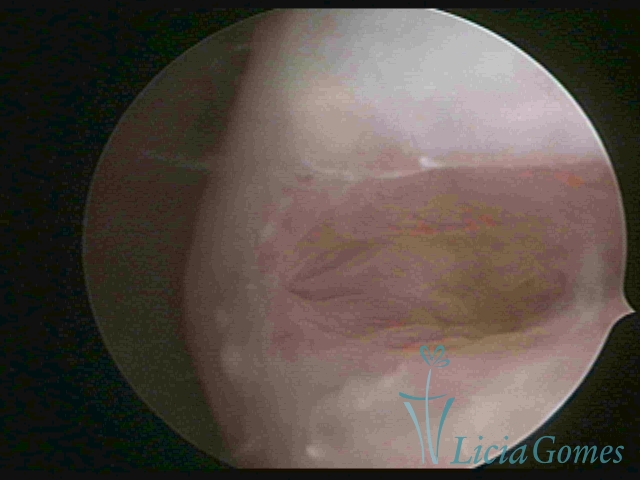

Primeira porção ou setor proximal ou setor inferior:

Durante a fase proliferativa, encontramos muco claro e cristalino pouco aderente à óptica. As criptas e as papilas apresentam-se um pouco edemaciadas e vascularizadas, micro vesicular, lembrando cachos de uva.